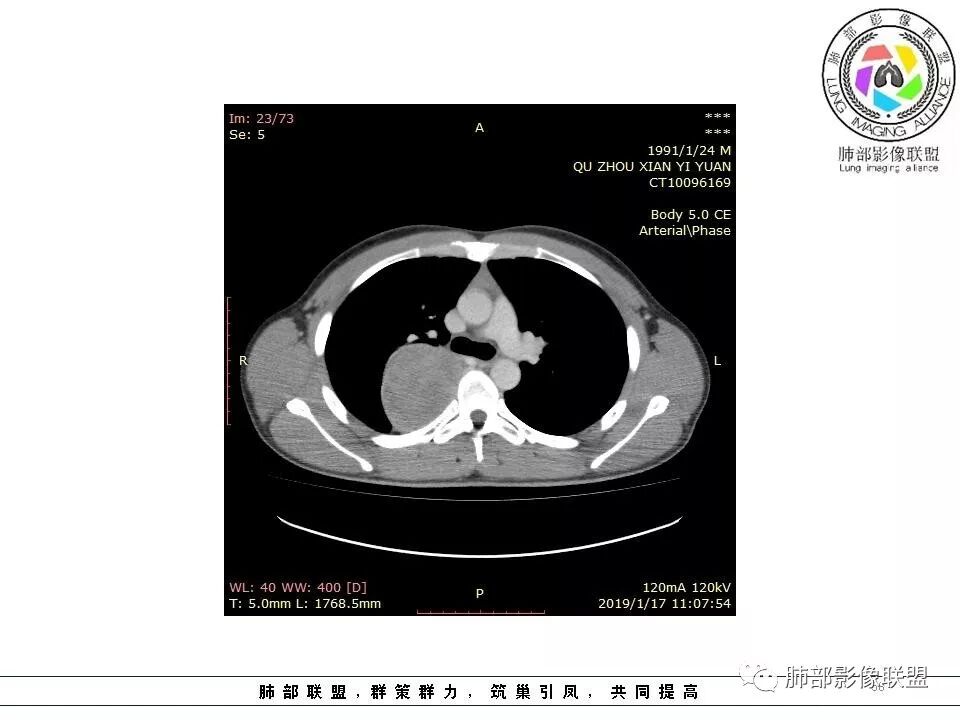

右后纵膈脊柱旁软组织占位,形态规则类圆,边缘光整,肺组织受压,胸膜尾,肋间动脉供血。中度不均匀延迟强化。

右后纵膈脊柱旁软组织占位,边界清晰,光整,肺组织受压。胸膜被掀起,肋间动脉供血,中度不均匀延迟强化。考虑神经鞘瘤,不除外纤维瘤

右后纵膈脊柱旁软组织影,与纵隔结构分界不清,形态规则类圆,边缘光整,肺组织受压,胸膜尾,肋间动脉供血。肺动脉推移,中度不均匀延迟强化。考虑神经来源,神经鞘瘤,神经纤维瘤二者不易鉴别。

青年男性,间断胸痛;右侧脊柱旁可见一类圆形软组织密度影,密度欠均匀,增强扫描呈轻中度持续强化,邻近肺组织及肺动脉推移,可见肋间动脉供血,部分胸膜下脂肪可见,部分层面似见与右侧椎间孔相连。考虑后纵隔神经源性肿瘤。

2.肋间动脉病供血也提示肿块来自后纵隔?

4.静脉期轻度不均匀强化,注意不是环形强化,亦未见明确的“AB区”,这点也不支持神经鞘瘤。临床及病灶轻度强化都不支持副节瘤。

尽管神经纤维瘤的诊断确实有些出乎意外,但病例开阔了我们的视野。